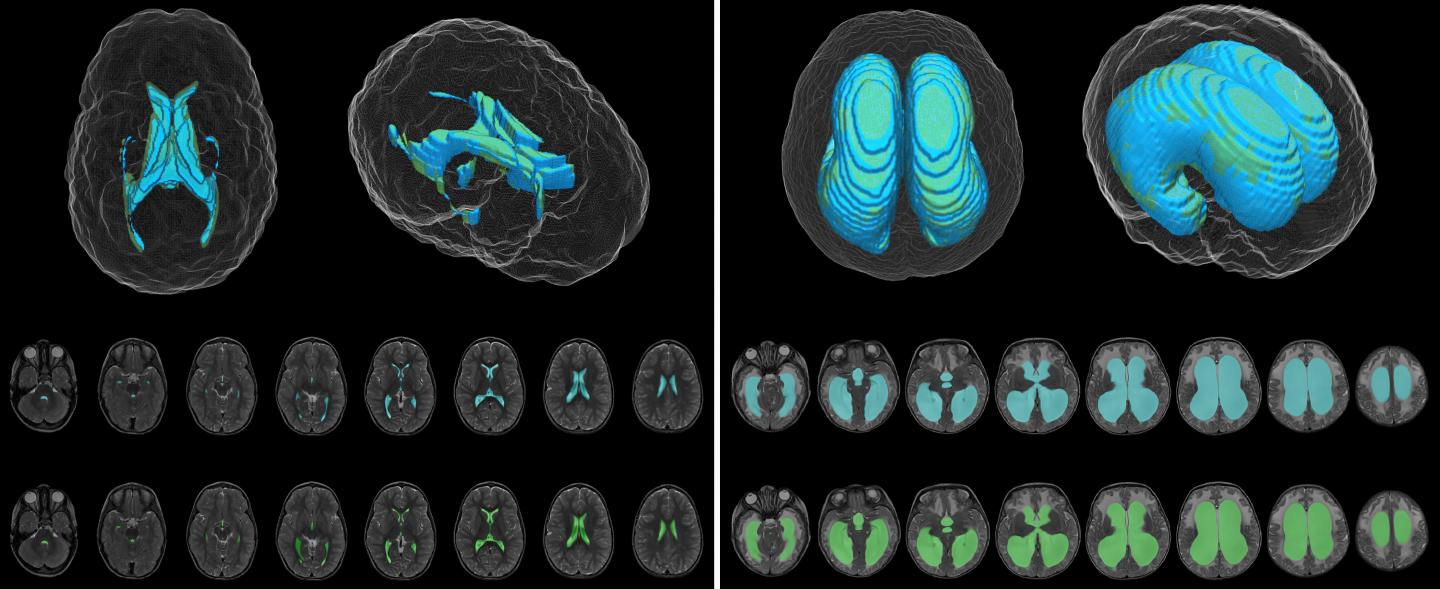

image: Deep learning model (blue) and ground truth manual (green) segmentation of representative control (left) and hydrocephalus (right) T2-weighted MR images. view more

The DL model was designed to produce automatic ventricle segmentation (delineation of ventricle borders on imaging) and volume calculation. To examine the efficiency of the model, the authors compared these two processes to the gold standard of manual segmentation and volume calculation and to the use of FreeSurfer research software. The authors used the Dice similarity coefficient (0 to 1) to assess segmentation accuracy and linear regression to assess volume calculation.

According to the authors, when compared to manual segmentation, "model segmentation performed with an overall Dice score of 0.901 (0.946 in hydrocephalus, 0.856 in controls)." These numbers show great accuracy, with even better accuracy evident when used in patients with hydrocephalus. When used to assess segmentation accuracy in the patients at Utah Primary Children's Hospital, the Dice score was 0.926.